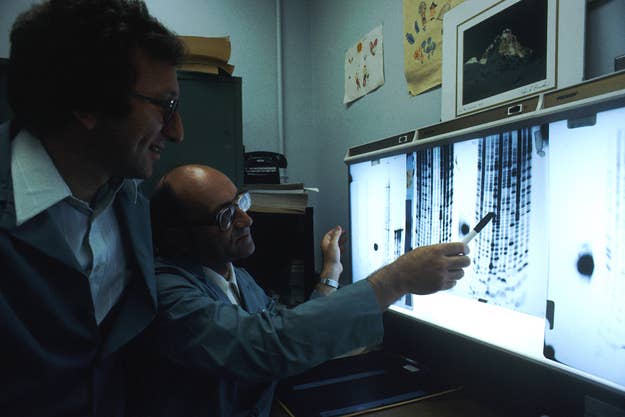

1. Advanced genomics and personalized medicine.